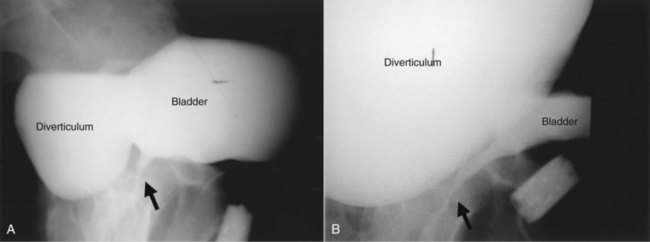

Acquired (also termed “secondary”) diverticula occur most commonly in the setting of bladder outlet obstruction or neurogenic vesicourethral dysfunction. Similar to the congenital type, these diverticula are also located most commonly at the ureterovesical hiatus (Van Arsdalen and Wein, 1992) but also occur elsewhere in the bladder. Acquired diverticula in males usually occur after age 60, which corresponds to the age of the development of prostatic enlargement (Fig. 78–2). Bladder outlet obstructions, including those due to benign and malignant disease of the prostate or urethral stricture, are commonly associated factors in adults, although obstruction is not considered to be present in all cases (Blacklock et al, 1983). Acquired diverticula are often multiple, typically found in association with significant bladder trabeculation (Wesselhoeft et al, 1963), and much more common in males than females (Senger et al, 1952; Pool and Hacker, 1966). Bladder diverticula in females are uncommon (Gillon et al, 1988) and quite rare in the absence of obstruction (Safir et al, 1998) (Fig. 78–3). Historically, the reported prevalence of moderate- to large-sized bladder diverticula in association with “prostatism” is approximately 1% to 6% (Burns, 1944). It is important to note that an acquired bladder diverticulum may also be found in children and young adults secondary to a number of conditions, including bladder neck dysfunction, posterior urethral valves, and neurogenic vesicourethral dysfunction. If the diverticulum encompasses the ureteral orifice in the setting of a neurogenic bladder and vesicoureteral reflux, it is termed a “Hutch” diverticulum (Hutch, 1952). These diverticula may also occur in the setting of dysfunctional voiding.

Figure 78–3 Bladder and urethral diverticula in a female. A, MRI of a bladder diverticulum. B, Endoluminal MRI demonstrating urethral diverticulum (arrow points to urethral diverticulum). B, bladder; D, bladder diverticulum.